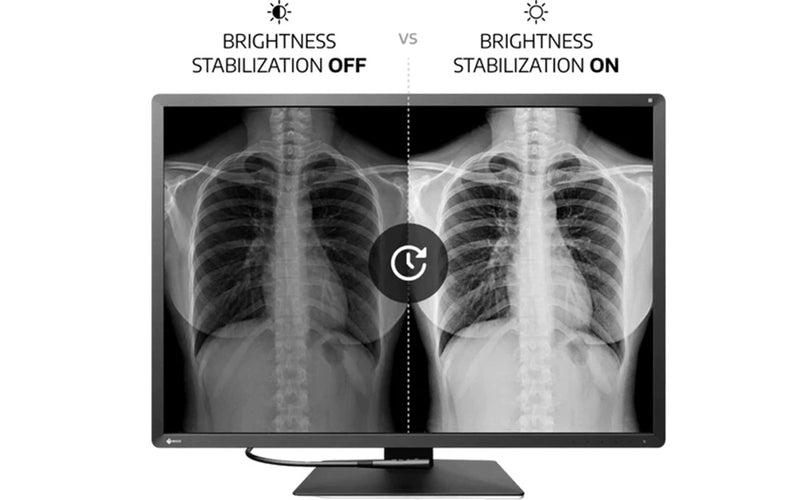

Σταθερή οθόνη χρησιμοποιώντας το AI

Το χρώμα και η φωτεινότητα μιας οθόνης LCD μπορεί να μετατοπιστεί λόγω μεταβολών της θερμοκρασίας περιβάλλοντος και της θερμοκρασίας της οθόνης. Οι οθόνες Radiforce της ιατρικής απεικόνισης είναι εξοπλισμένες με αισθητήρα θερμοκρασίας για την ακριβή μέτρηση της θερμοκρασίας μέσα στην οθόνη και την εκτίμηση της θερμοκρασίας του περιβάλλοντος περιβάλλοντος. Με αυτήν την τεχνολογία, το Eizo Radiforce RX1270 προσαρμόζεται σε πραγματικό χρόνο, έτσι οι διαβαθμίσεις, το χρώμα, η φωτεινότητα και άλλα χαρακτηριστικά συνεχίζουν να εμφανίζουν με ακρίβεια.

Επιπλέον, το EIZO χρησιμοποιεί AI (τεχνητή νοημοσύνη) στον αλγόριθμο εκτίμησης του RX1270, ώστε να μπορεί να διακρίνει μεταξύ των μεταβαλλόμενων προτύπων θερμοκρασίας για να υπολογίσει μια ακόμη ακριβέστερη διόρθωση.